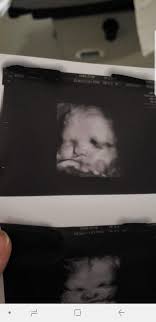

If the 2D ultrasound does not demonstrate two nasal bones then 3D ultasound may be useful. An ultrasound scan There is no risk to the baby from either of these procedures. October 15 2018 Shane Dale According to the National Down Syndrome Society NDSS during the normal fertilization of a womans egg by a mans sperm the resulting nucleus of each cell in a fetus contains 23 pairs of chromosomes half of which are inherited from each parent.

For this reason 3D ultrasound reconstruction of the nasal bone and other facial bones is useful. At this stage the babys legs arms fingers and toes should be fully formed. Mothers should not be encouraged to have an ultrasound called a.